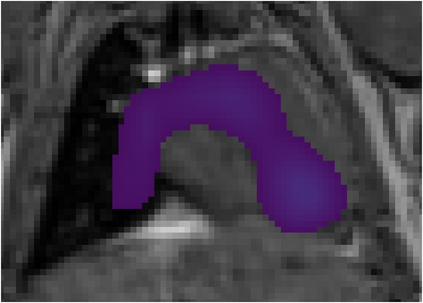

Various imaging modalities allow for time-dependent image reconstructions from measurements where its acquisition also has a time-dependent nature. Magnetic particle imaging (MPI) falls into this class of imaging modalities and it thus also provides a dynamic inverse problem. Without proper consideration of the dynamic behavior, motion artifacts in the reconstruction become an issue. More sophisticated methods need to be developed and applied to the reconstruction of the time-dependent sequences of images. In this context, we investigate the incorporation of motion priors in terms of certain flow-parameter-dependent PDEs in the reconstruction process of time-dependent 3D images in magnetic particle imaging. The present work comprises the method development for a general 3D+time setting for time-dependent linear forward operators, analytical investigation of necessary properties in the MPI forward operator, modeling aspects in dynamic MPI, and extensive numerical experiments on 3D+time imaging including simulated data as well as measurements from a rotation phantom and in-vivo data from a mouse.